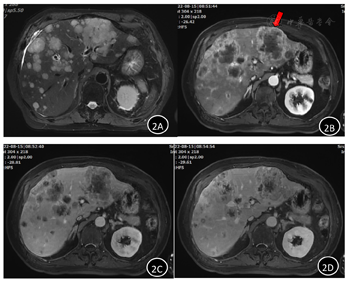

影像学检查:1.全身PET-CT示,左下肺软组织密度肿块,呈高代谢,考虑肺癌伴阻塞性炎症、肺不张;伴左胸腔少量积液;伴左肺门区、纵隔内、右胸廓入口区、肝门区、腹膜后腹主动脉旁多发淋巴结肿瘤转移;伴肝内肿瘤转移;伴胸11椎体肿瘤转移。PET-CT显示由于阻塞性肺炎伴肺不张暂不能清楚分辨左下肺占位边界,并可见伴肝内多发肿块(图1)。2.上腹部MRI示,肝脏弥漫性团块影,考虑多发转移瘤。左肝较大占位(红色箭头所指处)动脉期表现为周边环形强化征(图2)。

(3)原发性肝恶性肿瘤:包括肝细胞癌、胆管细胞癌和混合型肝癌,其中以肝细胞癌(hepatocellular carcinoma,HCC)最常见,可占原发性肝癌75%~85%。甲胎蛋白(alpha-fetoprotein,AFP)检测是目前诊断原发性肝细胞癌最好的早期诊断方法,在影像上可有典型"快进快出"表现[4]。而CA199和CEA是诊断ICC最常用的血清标志物[5],在动态增强检查中可有动脉期病灶周边强化表现,AFP通常阴性。本例患者上腹部MR,可见在增强后左肝肿块明显不均匀强化,其周边有强化影,目前ICC诊断待排。

(4)继发性肝恶性肿瘤:继发性肝癌一般没有肝脏严重病变的症状,影像上常表现为多个结节型病灶,典型征象为增强扫描可见环形强化的"牛眼征",AFP一般不升高。患者的上腹部MR片中,可以见到多发的、体积较小的、均匀环形强化的牛眼征表现,且患者AFP阴性,均支持肝转移癌诊断,但目前肿瘤原发病灶尚不完全明确。

诊断ICC时,需注意与肝细胞癌、混合型肝癌及肝转移瘤等相鉴别。与HCC相比,ICC有着"延迟性强化"的显著鉴别点,另外,弥漫性T1高信号虽然不是HCC的典型特征,但在ICC中不发生,因此其有利于HCC的诊断而不是ICC的诊断。而混合型肝癌(mixed hepatocellular-cholangiocarcinoma,HCC-CCA)则是一种罕见的肝脏恶性肿瘤,兼具有ICC和HCC的特征,表现为侵袭性病程且预后不良。肝脏作为恶性肿瘤偏好转移的脏器之一,在诊断ICC时还必须与肝转移瘤(liver metastases)进行鉴别。肝转移瘤的影像表现多种多样,其影像特征在很大程度上取决于各种原发肿瘤特异性因素。"牛眼征"是转移性肝癌的典型CT增强征象,可见于任何肝转移瘤,但多见于腺癌的肝转移,表现为病灶周边有晕环,中央乏血供而呈低密度。此外,肝转移瘤在MRI上表现为T1像稍低信号,T2像稍高信号,T2WI还可有瘤周高信号环的特殊征象,增强扫描各期均可呈环形强化,强化程度一般小于肝实质[8]。

本例患者以胸闷、气喘、咯血为首诊症状,体格检查阳性体征有左下肺呼吸音弱、右肋下三横指处触及肝下界,结合辅助检查提示CEA升高、左下肺不均匀密度肿块影继发阻塞性肺炎,均支持初步诊断为原发型肺癌合并肝转移瘤,后经完善两处病灶的病理检查,证实为肝内胆管癌伴肺转移。分析本病例,造成诊断错误主要原因有:(1)本例患者首诊症状突出表现为肺部症状,且在病史中否认ICC常见发病危险因素存在,导致初步诊断时过分关注肺部病变可能而轻易忽视其他疾病。回顾影像学表现,上腹部肿块很可能为ICC在本例中具有提示意义的体征,但由于合并数个体积较小的典型肝转移瘤存在,也致使在初步诊断中,简单片面地将所有肝脏结节与肿块用肝转移瘤这一诊断来解释。(2)肝内胆管癌影像学表现与肝转移瘤有一定的相似性。ICC在MR增强中的表现强调静脉期及延迟期渐进性强化的动态特点,若只简单分析动脉期肝脏病灶周边环形强化表现,则与肝转移瘤影像表现难以鉴别。在本例的初步诊断中,只单纯看到肝脏MR增强时动脉期环形强化的征象,未进一步分析静脉期和延迟期的特点,局限了本例的鉴别诊断思路。